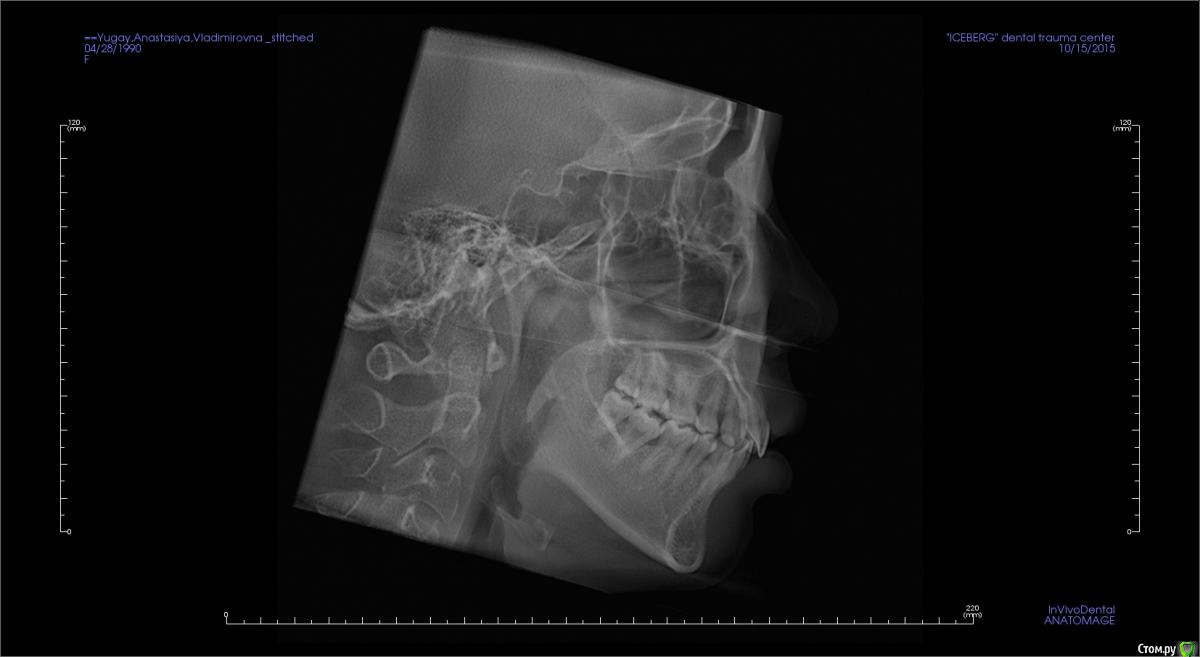

Головные боли, артроз ВНЧС, дистальный глубокий прикус, удалены 4ки на вч и 5 на нч

Сейчас мне 25 лет. С детства был дистальный глубокий прикус, зубы на верхней челюсти выпирали вперед, на нижней челюсти присутствовала скученность, из-за чего была удалена "мешающая" 5ка. Вероятно, этот зуб стоило сохранить.

В 2007-2008 гг. проходила ортодонтическое лечение с удалением 4ок на верхней челюсти. Резцовые зубы были перемещены назад, эстетически результат был удовлетворительным. Однако, проблема неправильного прикуса решена не была.

То, что эти боли могут быть следствием проблем с ВНЧС, узнала в последнюю очередь. МРТ показало, что у меня артроз суставов - 3 степени слева, полная вентрально-латерация дислокация суставного диска без репозиции; 1 степени справа, с репозицией, гипермобильность правого сустава. Асимметрии лица нет, однако рот открывается по S-образной траектории (почти не заметно), при широком открывании рта очень редко слышен щелчок, хрустов нет, слегка выпирает правый сустав. Заключение по МРТ с подробным описанием в приложении.

Заключение по МРТ, ОПТГ, цефалограмма в боковой проекции (справа и слева) и фото зубов - в приложении.

Все снимки по результатам КЛКТ (5 мб) можно скачать по ссылке https://www.dropbox.com/s/4c026r3ewd8zz0l/KLKT.zip?dl=0